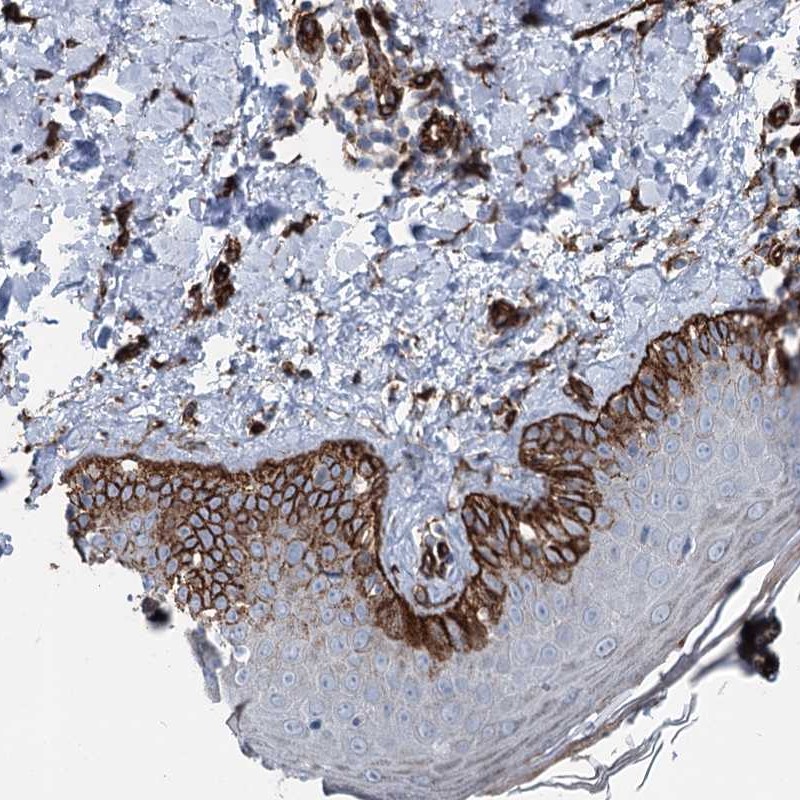

Immunohistochemical staining of human skin shows strong cytoplasmic positivity in basal cells of squamous epitheium.